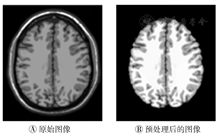

测试所用软件系统中,操作系统为Microsoft Windows 10,软件平台为MATLAB 2016B;硬件系统中,CPU为Intel Core i5 6400,内存为8 GB。为了验证分割算法的性能,首先使用BrainWeb脑部MR仿真数据集中T1加权图像进行实验。图2A为BrainWeb数据集中,处理前后的T1加权像的第100副断层图像,其噪声等级为0%,强度不均匀性为40%。分割后脑白质、灰质和脑脊液的DSC系数分别为99.12、96.14和90.16。

由于受脑部MR图像的强度不均匀性影响,直接使用OTSU多阈值分割结果不准确,因此使用BFC tool[7]去除强度不均匀性。图1A为图2B脑部图像对应的直方图,图1B为去除强度不均匀性后的直方图。可看出去除不均匀性后直方图的峰谷分布更为明显,更容易找到准确的最优阈值。图1的例子中,处理前的OTSU阈值为39、110和167,去除不均匀性后的OTSU阈值为35、101和153。